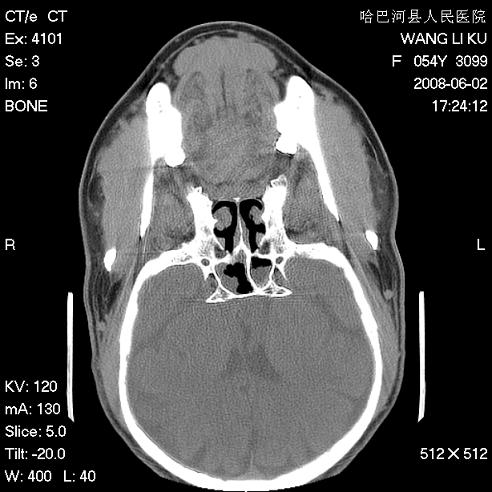

标题: CT13803:反复性鼻塞、流涕一年余 [打印本页]

标题: CT13803:反复性鼻塞、流涕一年余

副鼻窦炎,右上额窦积脓。左眼肌锥内见致密影,视神經受压

1.全组副鼻窦炎2.双侧上颌窦积液

1)全副鼻窦炎(左侧上颌窦黏膜下囊肿或息肉)。2)左眼眶肌锥内不规则小结节状软组织密度影;考虑为小血管瘤可能。建议行ct增强扫描检查。

全组副鼻窦炎,左侧肌锥内不规则形软组织肿块影,与眼外肌密度相当,左侧视神经受压,肿块与视神经及眼外肌分界清晰,眼外肌无增粗,眶壁无破坏,球后脂肪间隙不模糊,考虑良性改变,小血管瘤或神经源性肿瘤可能,建议增强扫描。

谢谢,增强扫描做了,眶内病灶与海绵窦同步明显强化,血管瘤